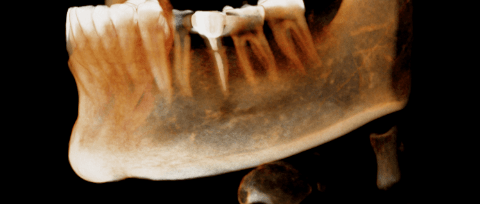

左下第一二大臼齒有膿包周囊袋過深,發現牙根斷裂 即拔即種當下清除發炎組織再補骨促進骨整合 左半邊咬合